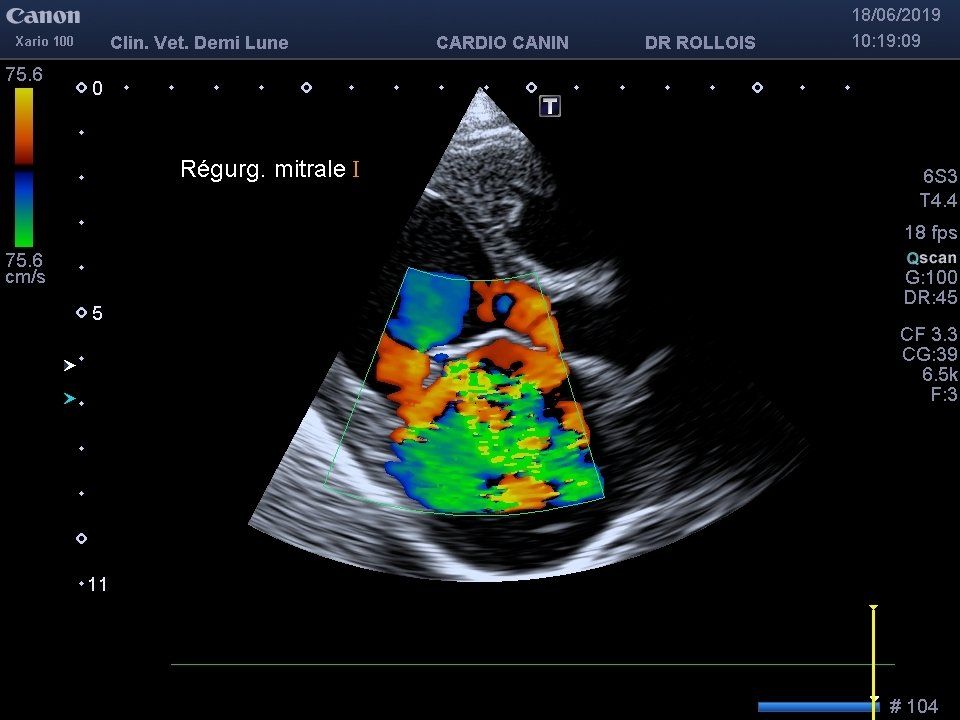

L’échocardiographie est indiquée dans l’exploration et le suivi des maladies cardiaques. Elle permet la visualisation des cavités cardiaques, ainsi que la contractibilité du muscle cardiaque et l’observation de la circulation sanguine. Elle peut être complétée par une mesure de la tension artérielle par un appareil Doppler et la réalisation d’un électrocardiogramme.